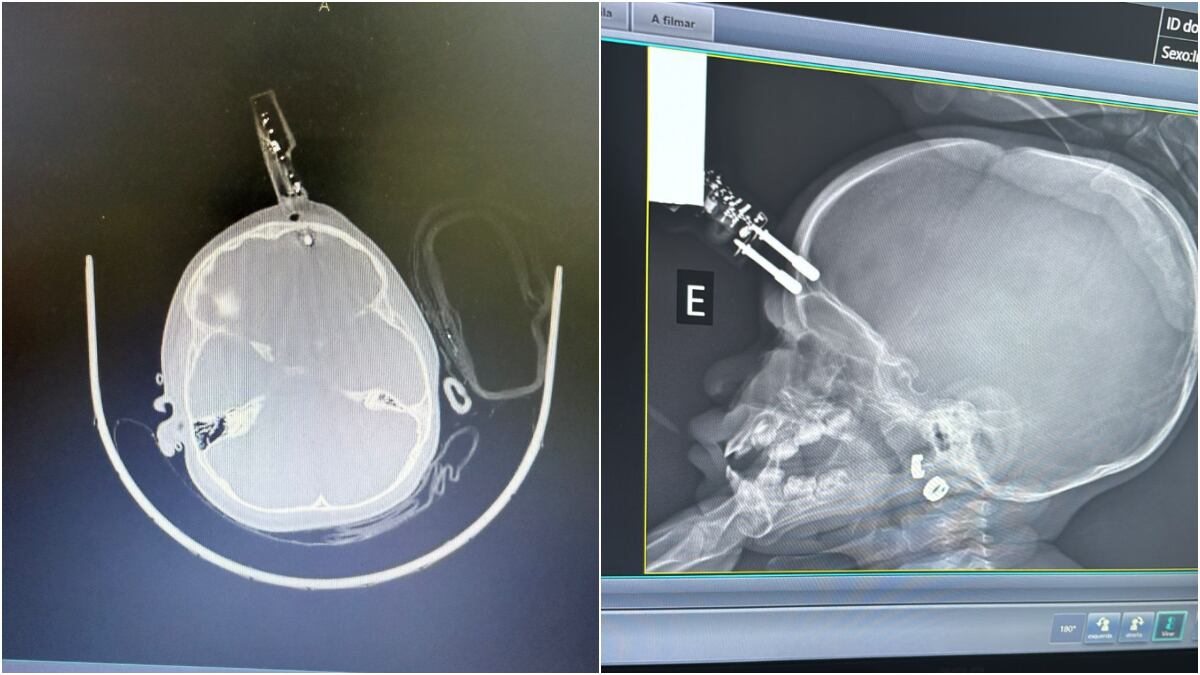

Uma menina de 1 ano e 4 meses ficou com um pino de carregador de celular cravado na testa após cair da cama dentro de casa, em Divinópolis, a 117 km de Belo Horizonte. A menina precisou passar por cirurgia para retirada do aparelho, que chegou a atingir o cérebro.

De acordo com o neurocirurgião Bruno Castro, que atendeu a criança, o acidente ocorreu na última segunda-feira (12), quando a mãe ouviu o choro da filha no quarto e a encontrou caída no chão, com sangramento e o objeto perfurando o crânio. “Era um carregador de celular comum. Um dos pinos estava cravado, atravessando o crânio na região frontal da criança”, afirmou.

“A tomografia mostrou que o pino estava machucando o cérebro, atingindo a ponta do lobo frontal”, explicou. Ele destacou que, nessa idade, o osso do crânio é muito fino, o que facilita perfurações em quedas.

Em seguida, a menina foi levada ao bloco cirúrgico, onde o objeto foi retirado. “Foi uma cirurgia rápida, tranquila, sem intercorrências. Estancamos um pequeno sangramento e corrigimos a falha”, disse Bruno Castro. Após o procedimento, a menina ficou 36 horas em observação no CTI pediátrico e apresentou boa evolução.